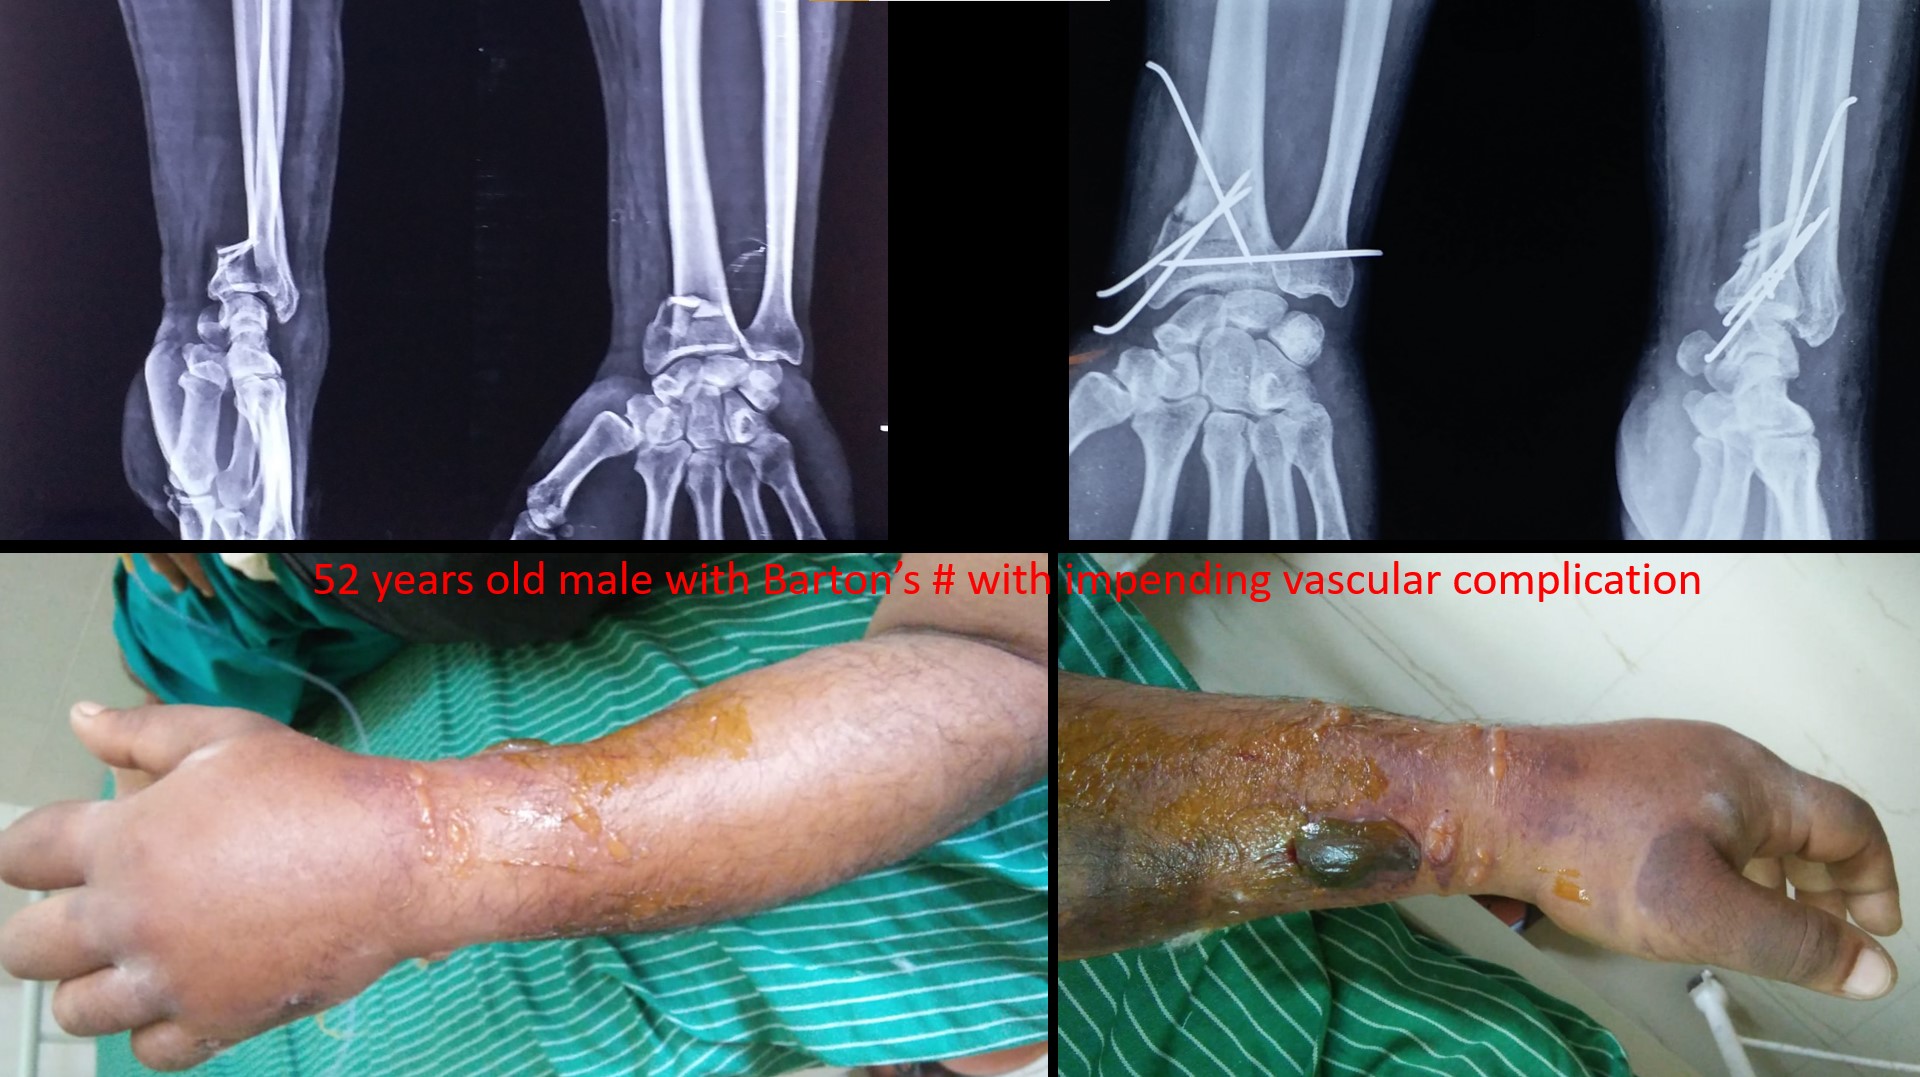

BARTON'S fRACTURE